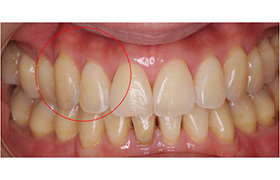

歯周病は治せます。なるべく歯を残せるような治療をしますが、再発を防ぐためには、その患者様の協力が非常に必要です。年をとっても自分の歯で食事ができるようにするためには、きちんとしたケアを実践しましょう。

Before

After